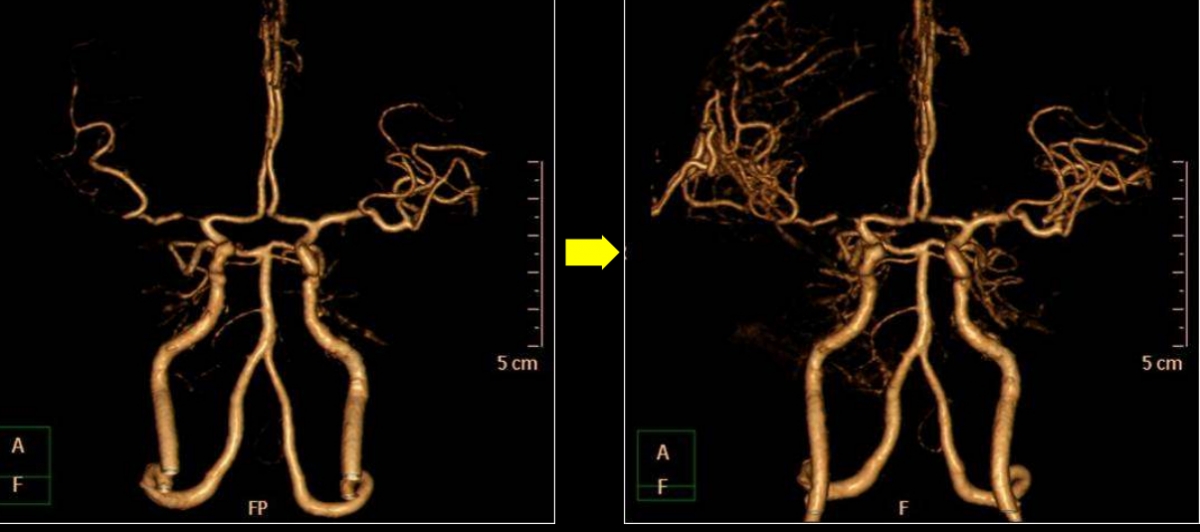

뇌 속 혈관이 부풀어 오르는 '뇌동맥류'도 발견 시 크기, 위험도 등을 고려해 예방적 차원에서 처치할 수 있다. 김문철 병원장은 "부푼 혈관을 클립으로 잡거나 백금 소재의 부드러운 코일을 채워 치료한다"며 "크기가 크고 여러 곳에 생긴 뇌동맥류도 이제는 촘촘한 스텐트 형태의 'WEB'이란 기구를 넣어 혈류를 억제하면 충분히 없앨 수 있다"고 말했다.